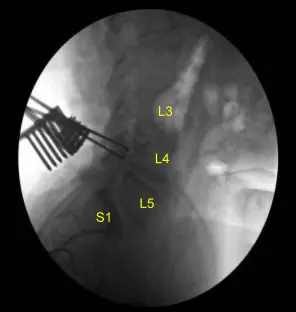

La unidad C-arm, que estaba cubierta de forma estéril, fue llevada al campo y utilizada para confirmar el nivel. Se fijó un arreglo de neuronavegación en la cresta ilíaca posterior superior derecha con dos clavos de Schanz tras infiltrarse con anestesia local y realizar incisiones #15 en la hoja con puñal.

El paciente estaba cubierto de forma estéril. Se realizó un TAC. Los datos se transfirieron al ordenador de neuronavegación. Se verificó la exactitud. Se utilizaron técnicas de neuronavegación para mordelinear hueso en caso de autoinjerto de artrodesis. Se utilizaron rongeurs Leksell, rongeurs Kerrison y taladro eléctrico de alta velocidad bajo irrigación estéril continua para realizar laminectomías completas de L4-5 y facetectomías, neurolizando completamente con la técnica de Penfield-Metzenbaum las raíces nerviosas L4, L5 y S1.